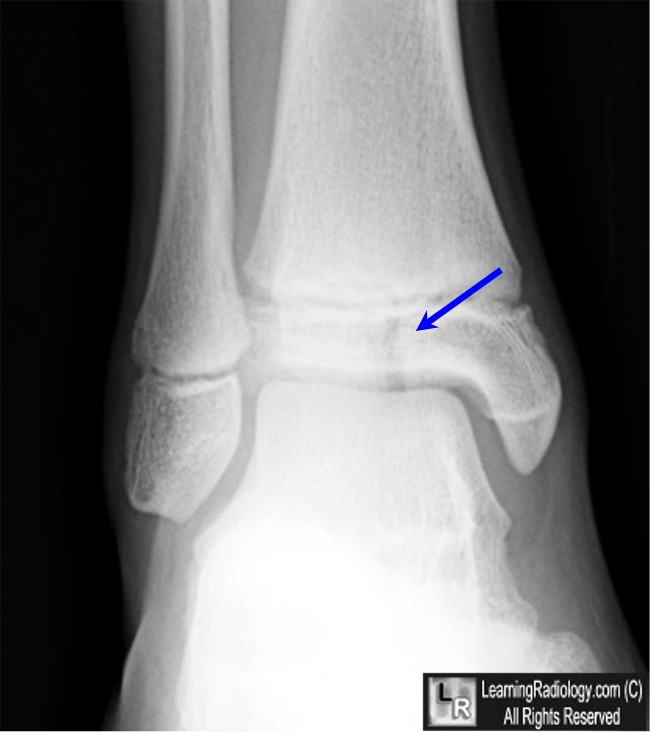

Pedal Fracture Definition Diagnosis is made with plain radiographs of the ankle. It is the anatomic equivalent of the bone that. Diagnosis is made with plain radiographs of the ankle. Treatment can be nonoperative or operative. Pedal bone fracture the coffin bone, also known as the pedal bone, third phalanx, distal phalanx, and os pedis , is located in the horse's foot. Looking for online definition of pedal fracture in the medical dictionary? Ankle fractures are very common injuries to the ankle which generally occur due to a twisting mechanism. The coffin bone, also known as the pedal bone or distal phalanx, is a small bone within the horse’s hoof. Fractures of the distal phalanx (pedal bone) usually occur as a result of trauma such as kicking a solid object, standing on a stone or fast exercise on hard ground. Such injuries can happen as a result of horses kicking out against solid objects,. This bone, which is rough and pitted in texture, is surrounded by the. Pedal bone fractures often occur as a result of a sudden traumatic injury to a horse’s foot.

From www.learningradiology.com

LearningRadiology Pedal Fracture Definition Pedal bone fracture the coffin bone, also known as the pedal bone, third phalanx, distal phalanx, and os pedis , is located in the horse's foot. Looking for online definition of pedal fracture in the medical dictionary? Diagnosis is made with plain radiographs of the ankle. The coffin bone, also known as the pedal bone or distal phalanx, is a. Pedal Fracture Definition.